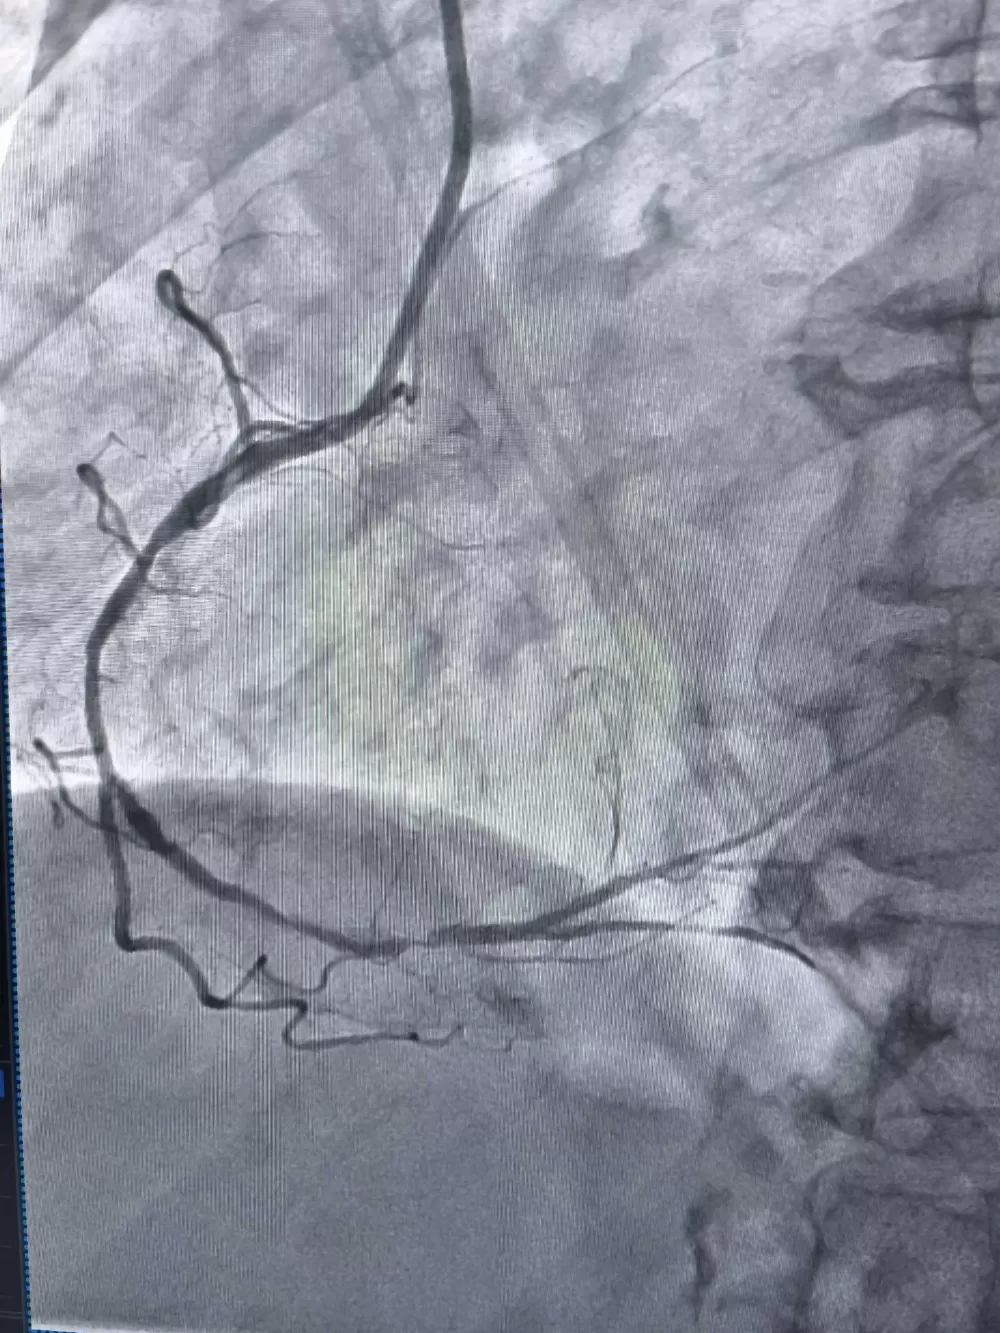

Пацієнтці діагностували серйозне звуження правої коронарної артерії. Розширити судину стандартним способом лікарі не змогли, навіть коли використали балон з тиском у 25 атмосфер – це вдесятеро більше, ніж у колесі автомобіля. Про це повідомили у Тернопільській обласній лікарні.

Тоді медики застосували ротаблятор. Це спеціальний прилад з буром, який покритий діамантовим напиленням. Він дозволяє обробити звапнілу бляшку в судині, фактично шліфуючи її. Після цього лікарі змогли встановити стенти.

Операція пройшла успішно. Жінці встановили стенти, які відновили нормальний кровотік у серцевій артерії.